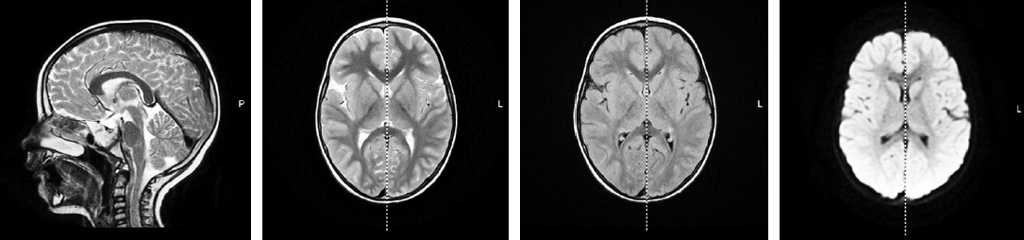

МРТ головного мозга 1,5 Тс: без структурных изменений (рис. 2).

Рис. 2. МРТ головного мозга 1,5 Тс пациента (режимы T2W, T1W, FLAIR, DWI): без структурных изменений